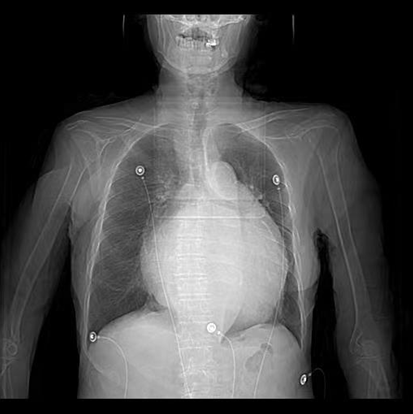

患者因“发作性气短20余年”之主诉入院,多次心脏超声诊断为风湿性心脏瓣膜病二尖瓣狭窄,此次因症状再发加重入院。经评估患者二尖瓣瓣口面积为0.67cm2,二尖瓣跨瓣压差为22mmHg,左房前后径94mm,左右径109mm,为重度风湿性二尖瓣狭窄伴罕见巨大左心房。在心内二科主任寿锡凌带领下,全科室充分讨论。因患者年龄大、基础情况差、无法耐受外科手术治疗,药物治疗不能解除瓣膜狭窄,只能选择经皮二尖瓣球囊扩张成形术。但鉴于患者巨大左心房已使心脏结构发生了巨大变化,单纯通过传统DSA影像结合经胸心脏超声指引下穿刺房间隔引起心脏破裂、心脏填塞、房间隔穿刺部位不佳影响手术操作、二尖瓣狭窄严重难以寻找二尖瓣瓣口、球囊扩张时球囊扩张位置不佳、术中难以即刻评估瓣膜扩张效果等均会导致手术失败进而威胁患者生命。考虑到心腔内超声宛如“心腔内的眼睛”可实时为术者提供心腔内的解剖结构毗邻关系,弥补传统DSA影像结合经胸心脏超声的不足,能为术者决策实时提供指导,确保手术能够安全、准确、顺利完成,最终决定为患者行心腔内超声指引下经皮二尖瓣球囊扩张成形手术。

此例手术由姚晓伟主任医师、韩稳琦主治医师、赵永勇主治医师通过心腔内超声指导下进行,通过心腔内超声精准构建心脏模型、直视下穿刺房间隔,后通过心腔内超声及左心房造影寻找狭窄的二尖瓣瓣口,并指引二尖瓣球囊扩张导管顺利经狭窄的二尖瓣口至左心室,在心腔内超声的指引下选择最佳位置以26mm球囊导管反复扩张狭窄的二尖瓣。术后第二天复查心脏超声,患者二尖瓣瓣口面积由术前0.67cm2扩大到术后1.69cm2,二尖瓣跨瓣压差由术前22mmHg降低至术后的16mmHg,左房前后径由术前94mm减小至术后92mm,左房左右径由术前109mm减小至术后102mm,并且球囊扩张后未引起明显的二尖瓣反流,患者心功能明显改善,自觉症状明显好转出院。

图一:患者胸片显示心影显著增大,以左心房增大为主